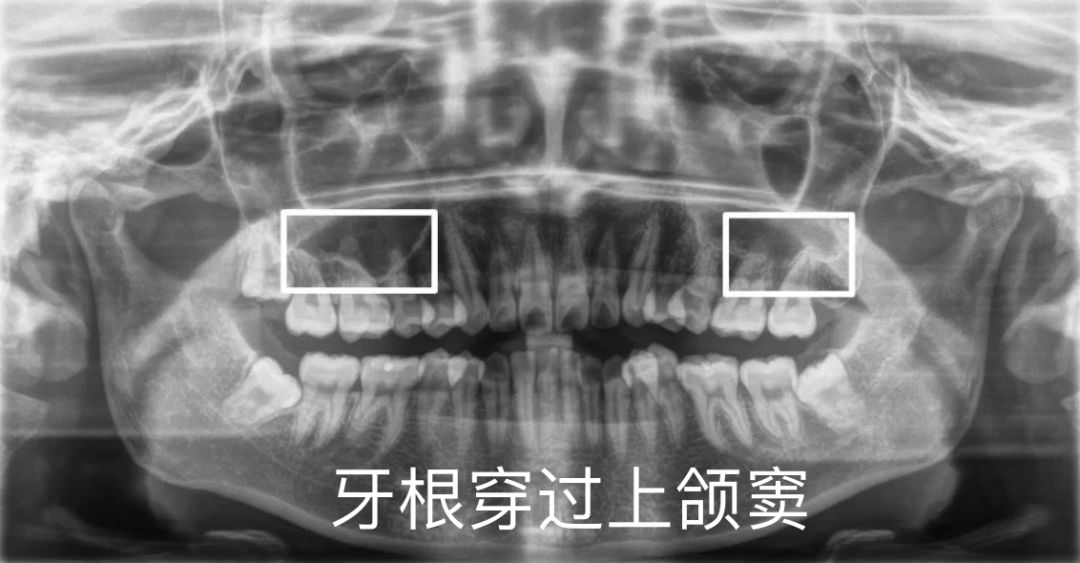

如果上颌牙的某些牙根进入了上颌窦内95那么这些牙齿在移动时受到的

牙根在上颌窦内还能矫正吗